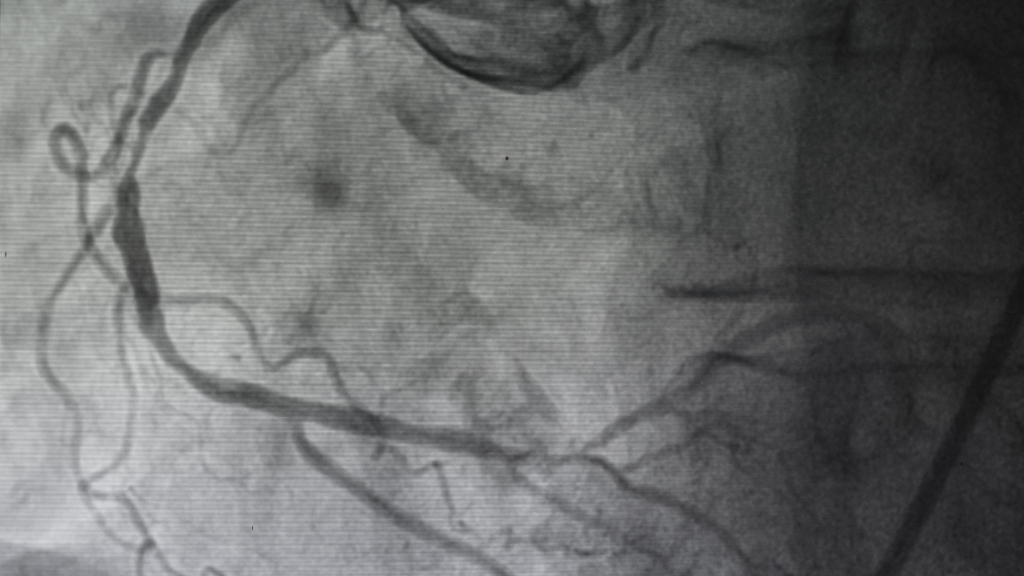

Chụp động mạch vành

Chụp động mạch vành là một kỹ thuật xâm lấn, thường được xem là phương pháp chẩn đoán giải phẫu quan trọng nhất trong xét nghiệm nhồi máu cơ tim.

Bằng cách sử dụng thuốc cản quang và tia X, bác sĩ có thể quan sát trực tiếp hệ thống mạch vành, xác định vị trí, mức độ và số lượng mạch bị tắc nghẽn. Đồng thời, thủ thuật này cho phép can thiệp tái thông ngay như nong mạch, đặt stent hoặc phẫu thuật bắc cầu. Dù chi phí cao và đòi hỏi trang thiết bị hiện đại, chụp động mạch vành vẫn là tiêu chuẩn vàng trong xác định và điều trị nhồi máu cơ tim.